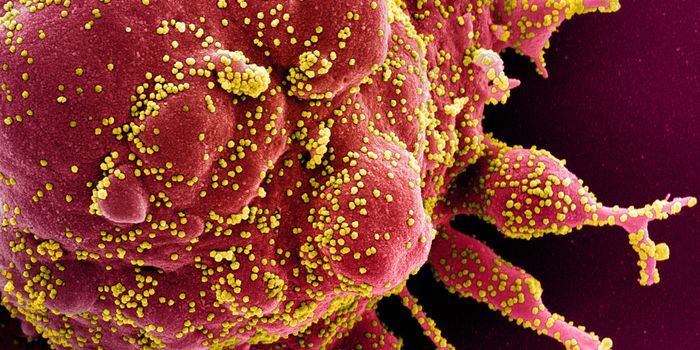

MAR 22, 2020MicrobiologyMore data is being gathered from an unfortunate and dramatic rise in the number of COVID-19 cases around the world.

APR 01, 2020MicrobiologyThere are a couple of different kinds of tests that researchers will be developing and clinicians will be using to disru ...

MAY 03, 2020Genetics & GenomicsThe origin of SARS-CoV-2, the pandemic virus that causes COVID-19, has become politicized as leaders seek to place blame ...

JUL 06, 2020MicrobiologyThe pandemic coronavirus has caused a wide range of different symptoms, and as time goes on, we may find that it can hav ...

JUL 05, 2020Cell & Molecular BiologyThe pandemic virus SARS-CoV-2 enters the body through the respiratory system to cause the illness COVID-19. But we know ...

JUN 29, 2020MicrobiologyVaccines that contain live attenuated viruses may be giving people some protection from serious cases of COVID-19 that i ...

FEB 22, 2021MicrobiologyReporting in Science, researchers have created an antiviral nasal spray that could help us get the COVID-19 pandemic und ...

SEP 01, 2021MicrobiologyIt's been generally assumed that people who get infected with SARS-COV-2 will develop antibodies to the virus, which cau ...